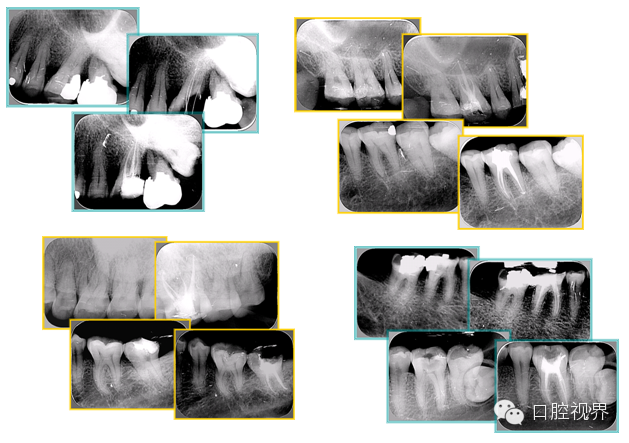

2. X 线片

共有 4 张 X 线片,分别是术前、诊断丝 、主牙胶尖确认、术后。

( 1 )术前:术前 X 线片用来了解牙齿的大概情况。术前预期为多根牙时 X 线片应偏头拍摄。

( 2 )诊断丝:根据术前 X 线片进行开髓、根管的初步预备后,需要插入诊断丝,用来指示工作器械位置。常用 10 号或 15 号扩大器作为诊断丝插入牙髓腔。

( 3 )主牙胶尖确认:通过术前预期和诊断丝诊断,明确工作长度、牙根走向,进行根管预备。之后应进行主牙胶尖(中锉)确认,已明确根管是否适合充填。

( 4 )术后:观察治疗效果。